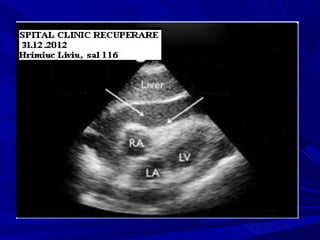

ECHO-CARDIOGRAPHYECHO-CARDIOGRAPHY

Signs of high fluid quantitySigns of high fluid quantity

Swinging heartSwinging heart

Signs of high pericardial pressureSigns of high pericardial pressure

RA diastolic collapseRA diastolic collapse

RV diastolic collapseRV diastolic collapse

LA, LV diastolic collapseLA, LV diastolic collapse

Signs of high systemic venous pressureSigns of high systemic venous pressure

IVC distensionIVC distension

< 50% collapse in inspiration< 50% collapse in inspiration